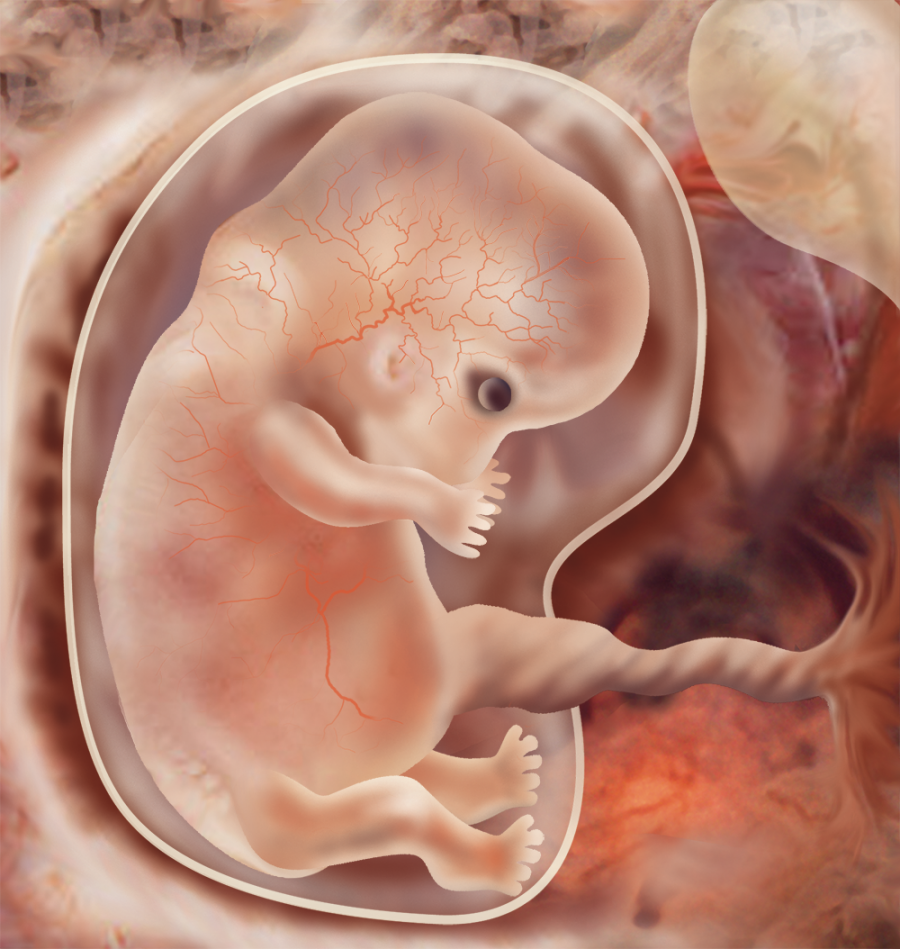

Удивительные фотографии эмбриона на 8 неделе беременности